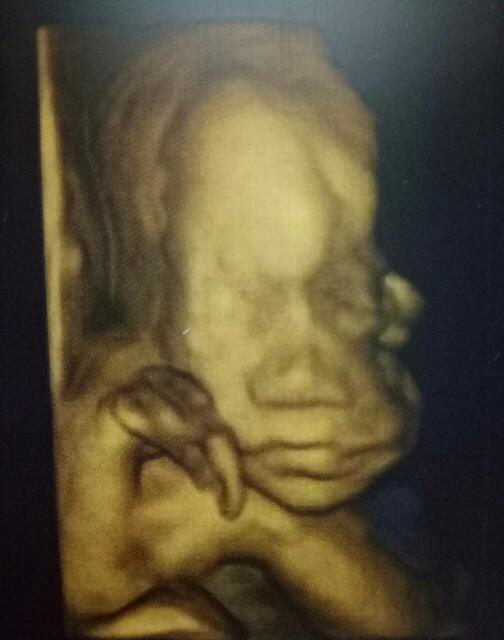

今天去医院做了系统B超,宝宝棒棒哒!顺利通过妈妈还看到了你在吃手手哟!小家伙,妈妈爱你

今天去医院做认坊了系统B超,宝宝棒棒哒!顺利通过😘妈筛险妈还看蔑安径到了你在吃手手哟!小家伙,妈妈爱你